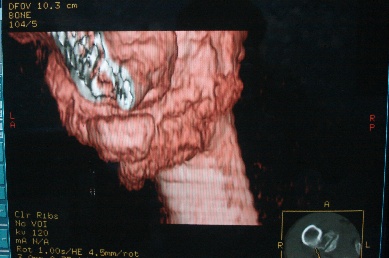

右上肢活动不便多年,最近加重。右肱骨肿瘤,请会诊!

骨软骨瘤恶变可能性大

右肱骨近断骨软骨瘤伴临近关节退变.有无恶变建议进一步检查.

右肱骨近断骨软骨瘤伴临近关节退变。

病变边缘轮廓清晰无骨质破坏,邻近软组织不肿胀,不支持肿瘤恶变。